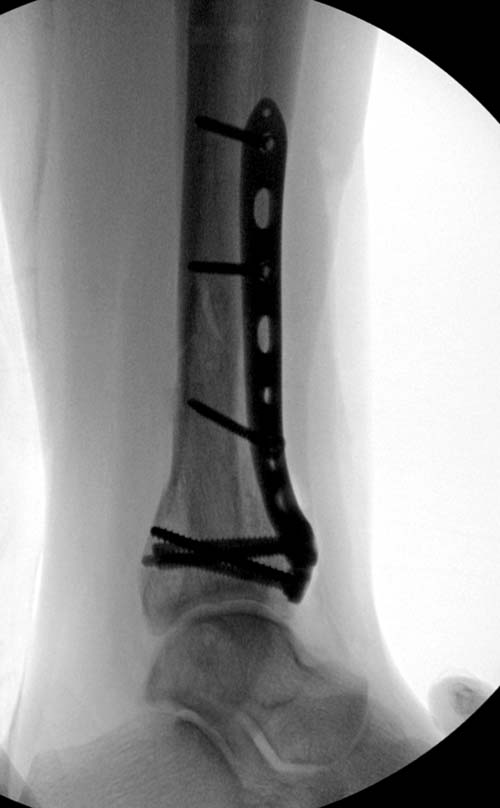

Первый случай, где перелом в результате падения с  небольшой высоты, где

мортиз рентген снимок показал отстутствие укорочения наружной

лодыжки и КТ срезы подсказали направления атаки. После такой фиксации

нет надобности в гипсовой повязке, брейс и через две недели движения в

суставе без нагрузки.